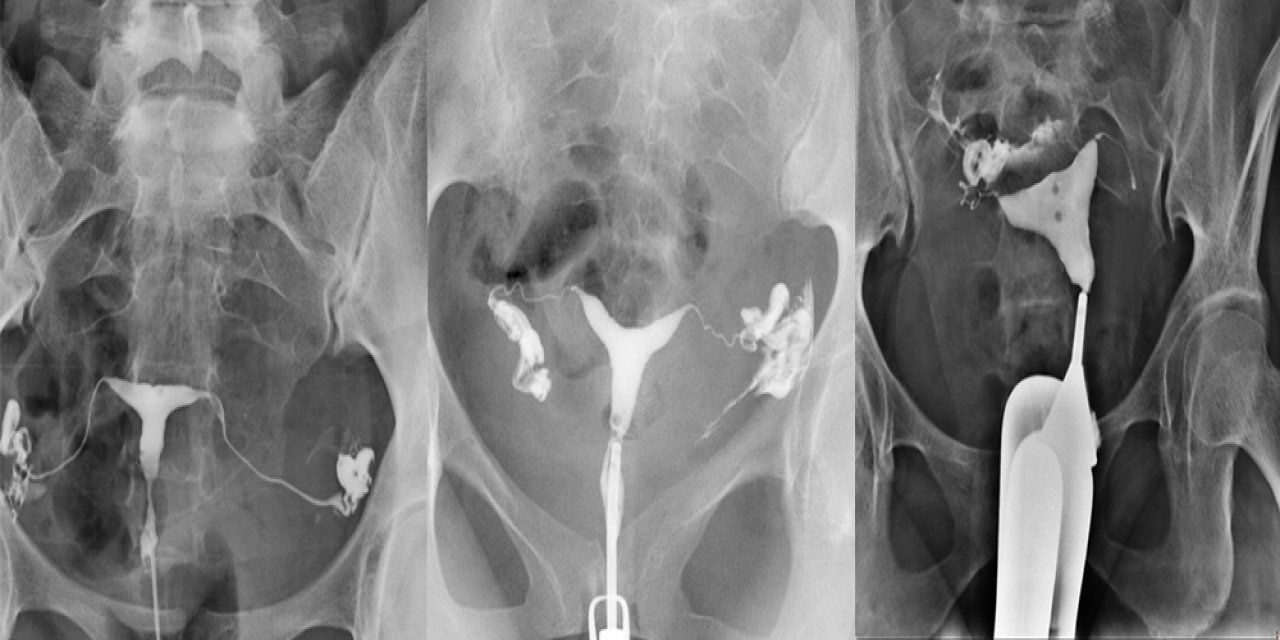

Algoloji uzmanları İzmir’de buluştu; ağrı pili uygulamasını akıllı gözlükle anlık olarak izledi